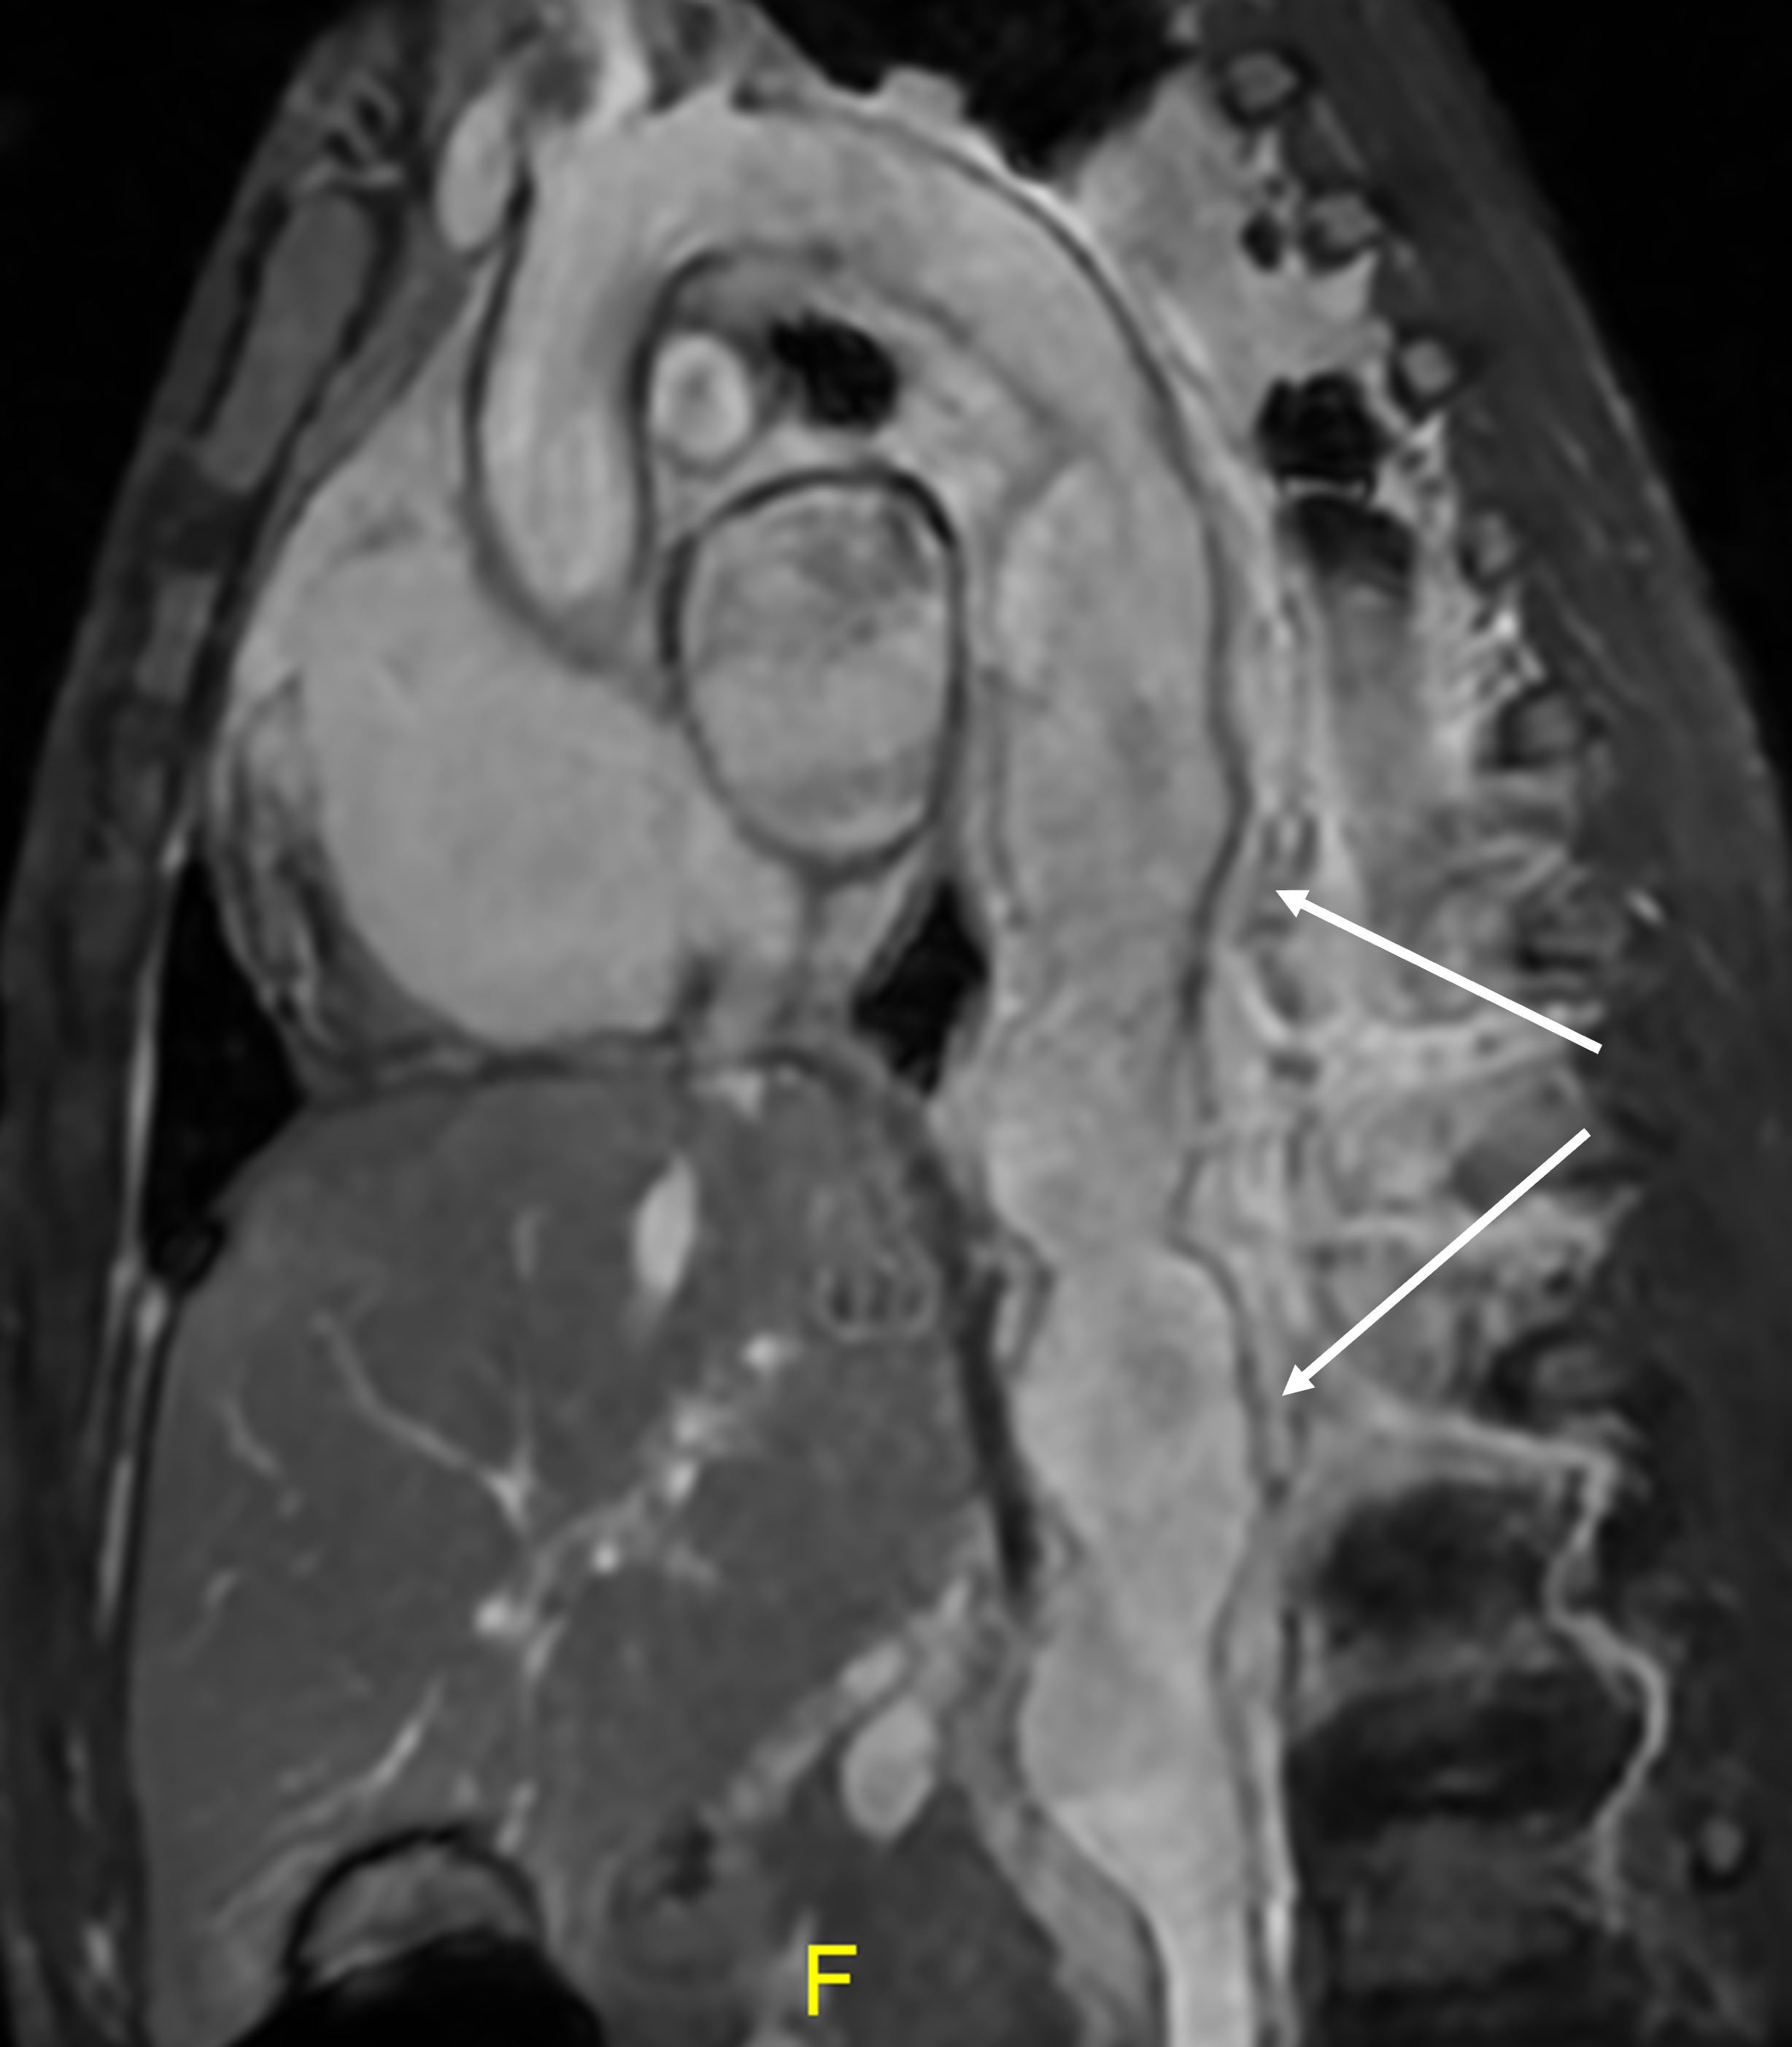

Diagnostic Techniques and Their Most Important Findings: MR angiography of the chest, abdomen, and pelvis (SIGNA Artist, GE Health, 1.5T) was performed. High resolution, post-contrast cardiac-gated 3D SSFP imaging of the chest (3D Whole Heart) was obtained and demonstrated marked irregularity and fusiform dilation of the aorta extending from the aortic arch through the iliac bifurcation (Image 1). There was severe dilatation of the left main coronary artery and proximal left anterior descending artery with normal sized coronary at the bifurcation (Image 2). Tissue characterization with fat-saturated pre- and post-contrast T1 weighted and T2 weighted sequences was performed. These demonstrated marked aortic wall thickening and enhancement consistent with active inflammation (Image 3). Findings were felt to be consistent with Takayasu arteritis with coronary involvement. He was started on heparin and methylprednisone and transitioned to clopidogrel, aspirin, rivaroxaban, optic and systemic prednisone, and infliximab infusion as an outpatient.

Image 1: Marked irregularity and fusiform dilation of the aorta extending from the aortic arch through the iliac bifurcation.

Diagnostic Techniques and Their Most Important Findings: MR angiography of the chest, abdomen, and pelvis (SIGNA Artist, GE Health, 1.5T) was performed. High resolution, post-contrast cardiac-gated 3D SSFP imaging of the chest (3D Whole Heart) was obtained and demonstrated marked irregularity and fusiform dilation of the aorta extending from the aortic arch through the iliac bifurcation (Image 1). There was severe dilatation of the left main coronary artery and proximal left anterior descending artery with normal sized coronary at the bifurcation (Image 2). Tissue characterization with fat-saturated pre- and post-contrast T1 weighted and T2 weighted sequences was performed. These demonstrated marked aortic wall thickening and enhancement consistent with active inflammation (Image 3). Findings were felt to be consistent with Takayasu arteritis with coronary involvement. He was started on heparin and methylprednisone and transitioned to clopidogrel, aspirin, rivaroxaban, optic and systemic prednisone, and infliximab infusion as an outpatient.

Image 1: Marked irregularity and fusiform dilation of the aorta extending from the aortic arch through the iliac bifurcation.